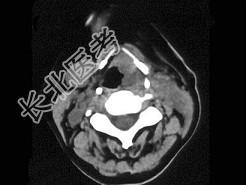

- 单项选择题女,54岁, 喉部异物感约3个月,PE: 左侧声带固定,可见肿物, CT如图,最可能的诊断是 ( )